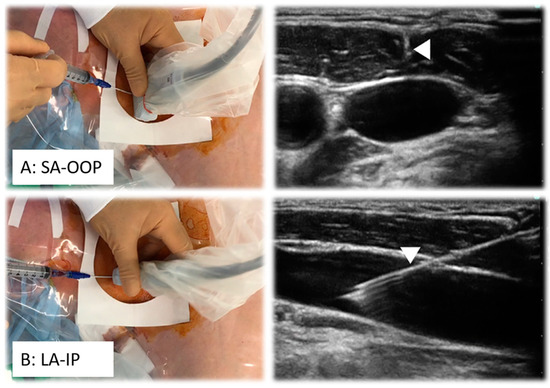

| Ultrasound (US) | Real-time imaging, widely adapted, non-radiation, versatile for peripheral vessel access, 2D and 3D options available | Limited penetration depth (25 cm max), instrument visibility depends on access site and orientation, high experience needed |